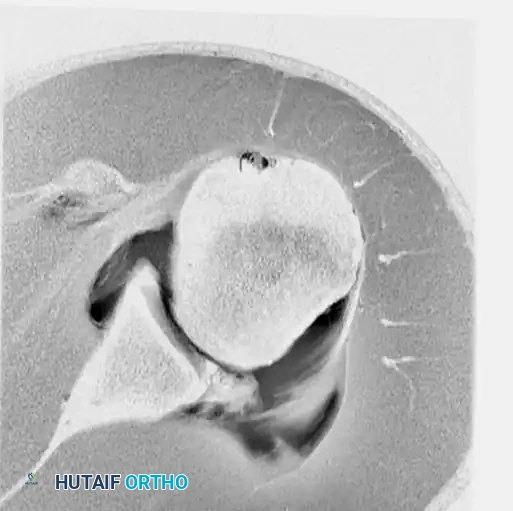

Preoperative magnetic resonance imaging (MRI) or MR arthrography is essential for identifying specific capsuloligamentous injuries. One such critical finding is the Humeral Avulsion of the Glenohumeral Ligament (HAGL) lesion, which can be easily missed if not specifically sought.

Figure 47-32 (A, B, C): MR angiograms demonstrating a HAGL lesion. Note the characteristic J-sign indicating the avulsion of the inferior glenohumeral ligament from its humeral attachment.